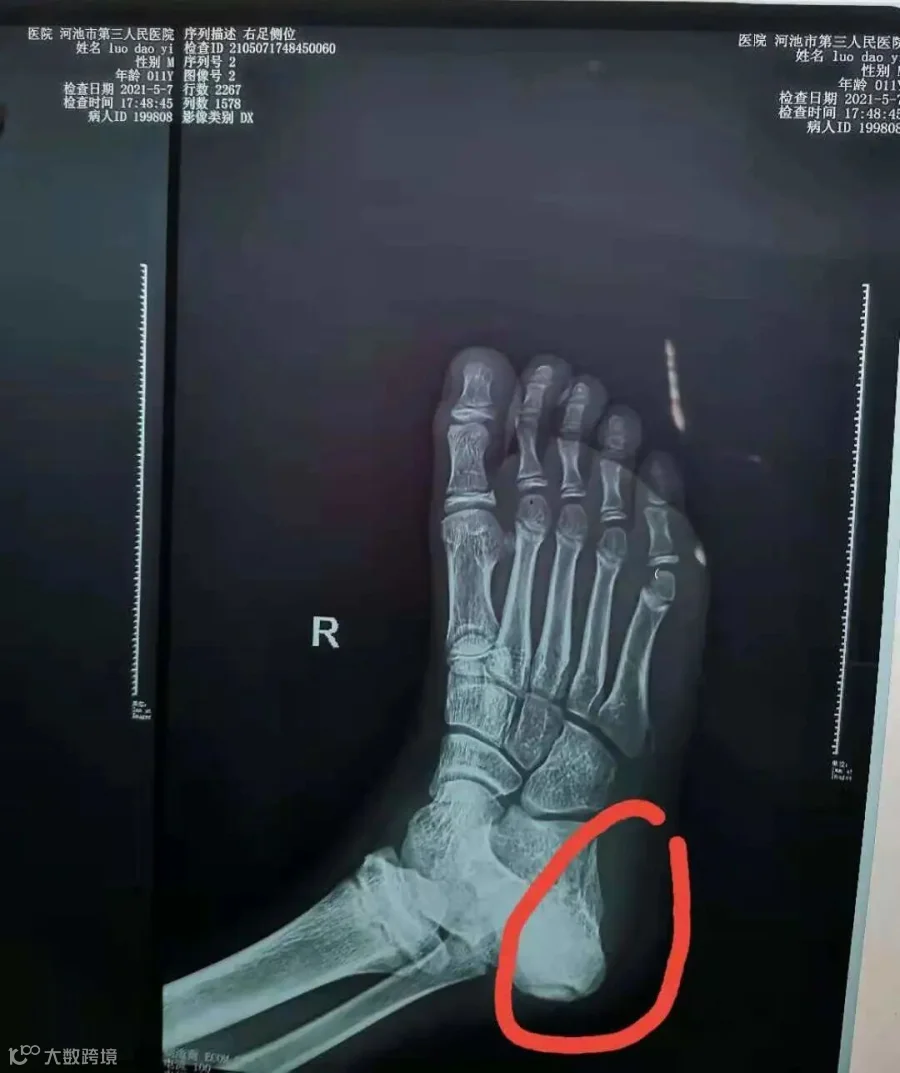

罗云(化名),11岁4月

治疗前